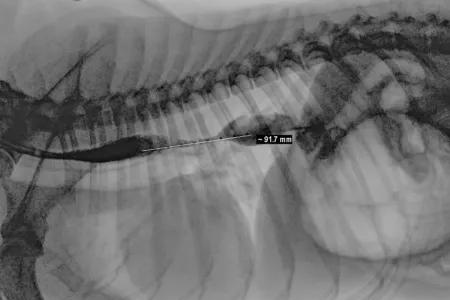

Clinicians performed fluoroscopy, an imaging technique that displays a continuous X-ray image, to monitor Colt’s digestive tract, and identified a 9cm narrowing in his oesophagus.

Xray of dogs chest showing restricted oesophagus

Colt's oesophageal stricture measured over 9cm in length.